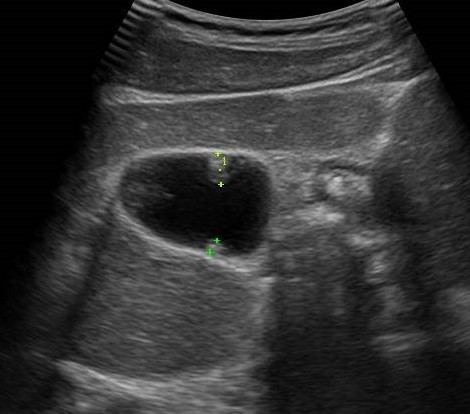

病変サイズもすぐに確認できます

またポリープや腫瘍、結石などの大きさの変化などもすみやかに確認できます。

炎症が改善しているのか、悪化しているのか、腫瘍の経過では腹水などが増えていないか、リンパへの再発が無いかなども確認できます。

大きな胆石が見つかることも!